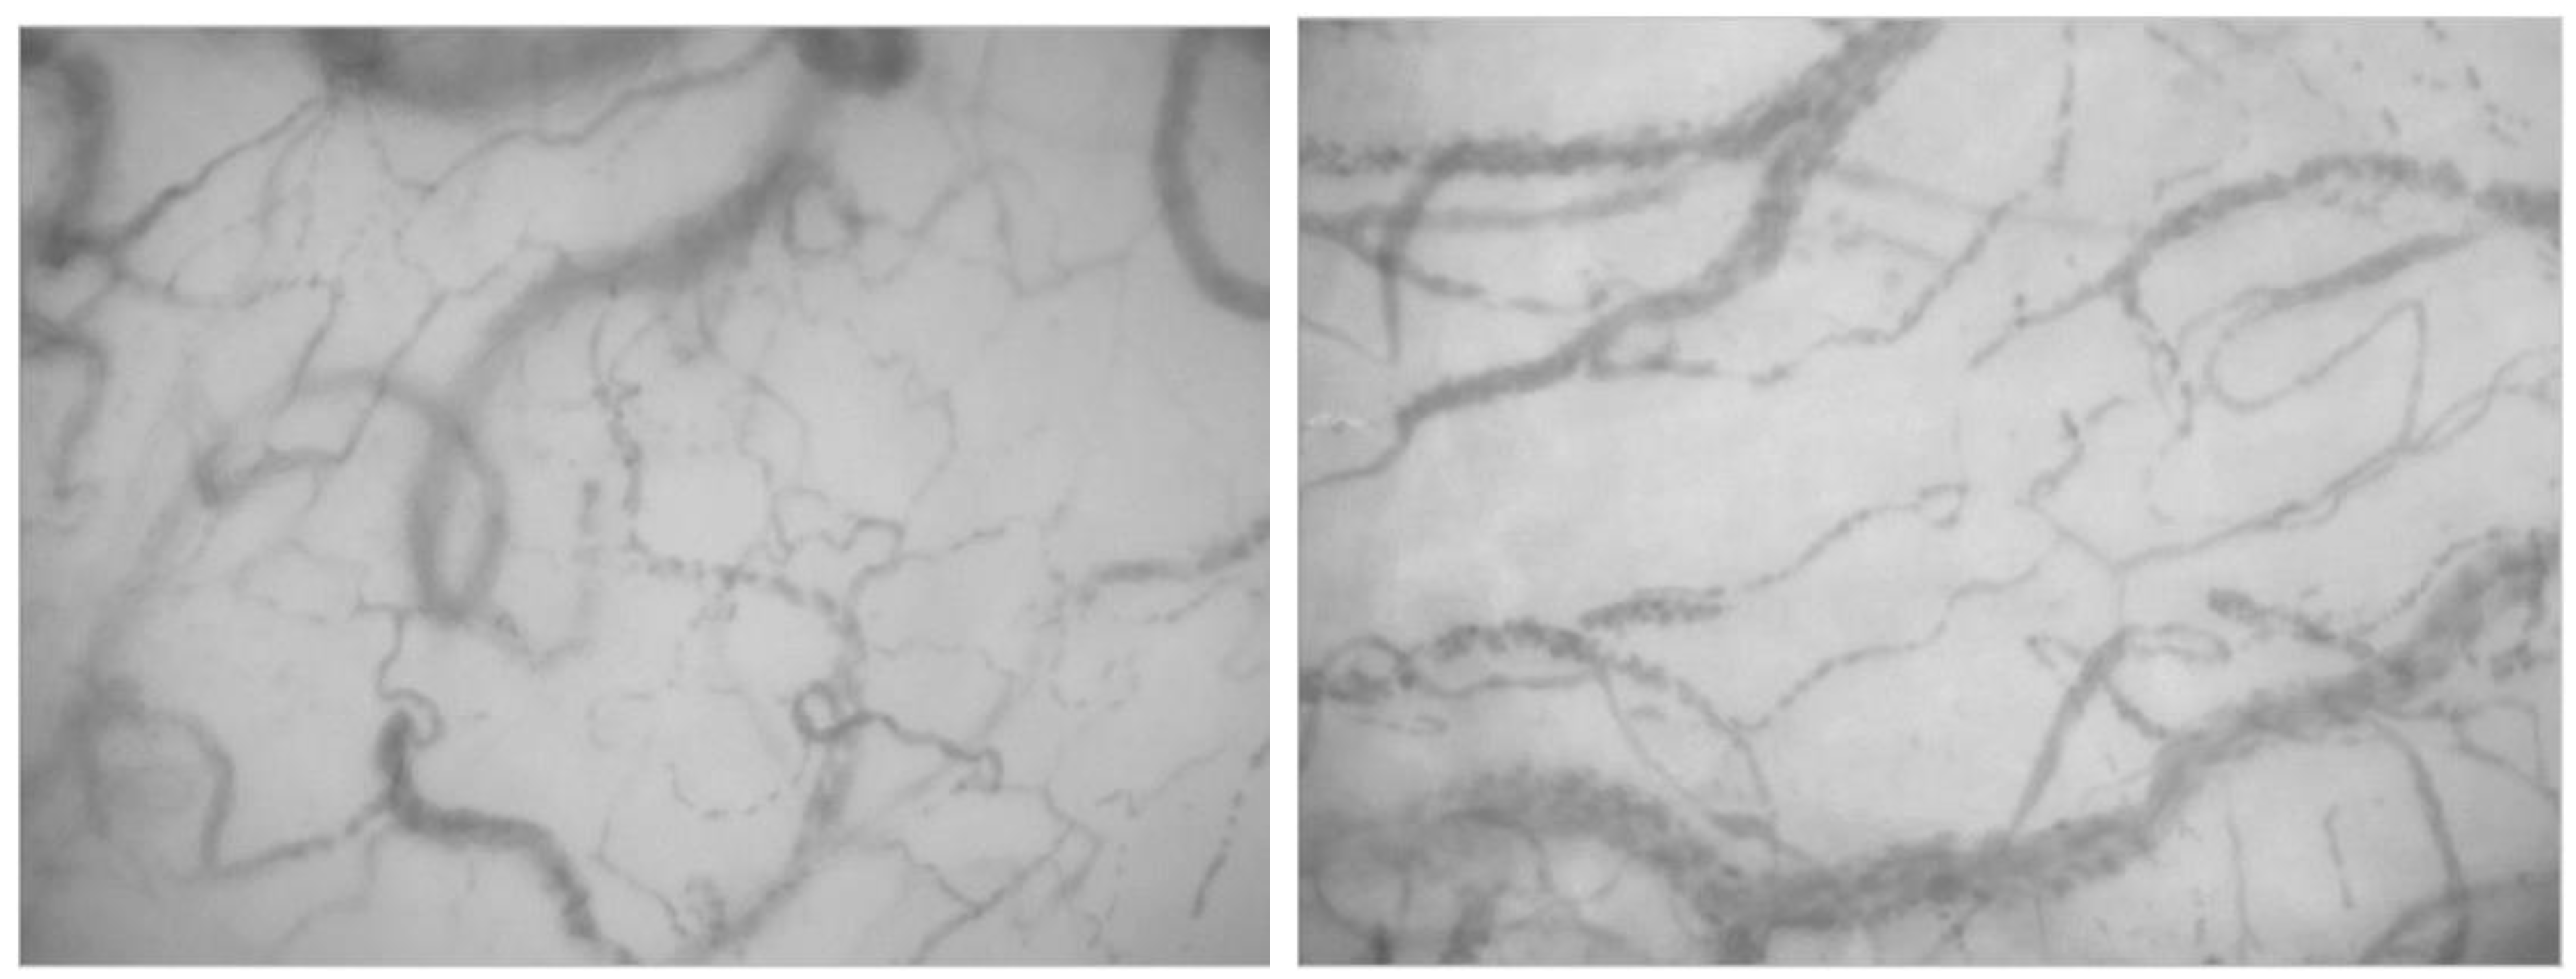

- Goedhart, P.T.; Khalilzada, M.; Bezemer, R.; Merza, J.; Ince, C. Sidestream Dark Field (SDF) imaging: A novel stroboscopic LED ring-based imaging modality for clinical assessment of the microcirculation. Opt. Express 2007, 15, 15101–15114. [Google Scholar] [CrossRef]

- van Elteren, H.A.; Ince, C.; Tibboel, D.; Reiss, I.K.M.; de Jonge, R.C.J. Cutaneous microcirculation in preterm neonates: Comparison between sidestream dark field (SDF) and incident dark field (IDF) imaging. J. Clin. Monit. Comput. 2015, 29, 543–548. [Google Scholar] [CrossRef]

- Gilbert-Kawai, E.; Coppel, J.; Bountziouka, V.; Ince, C.; Martin, D.; Caudwell Xtreme Everest and Xtreme Everest 2 Research Groups. A comparison of the quality of image acquisition between the incident dark field and sidestream dark field video-microscopes. BMC Med. Imaging 2016, 16, 10. [Google Scholar] [CrossRef]